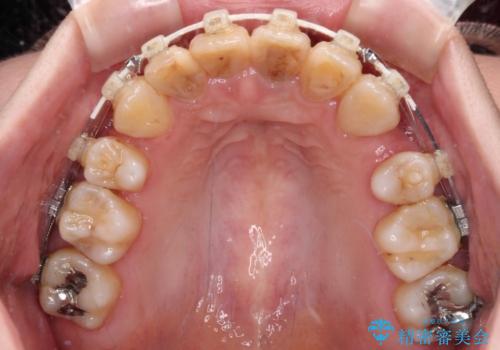

- 矯正装置

- 審美装置

口元の突出感はありませんが、前歯の重なりが著しいため、目立ちにくい表側のワイヤー装置にて、上下左右の第一小臼歯4本を抜歯して矯正治療を行うこととしました。

4本とも歯根部先端の骨が炎症により吸収していることがレントゲン写真から示唆されたため、矯正治療後に4本を再根管治療し、その後上顎6歯をオールセラミッククラウンにて補綴治療することとしました。